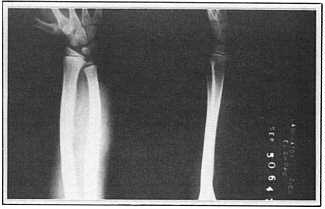

Photo 4: Follow-up X-ray of left arm, 8 years

post-treatment

(September 1978) |